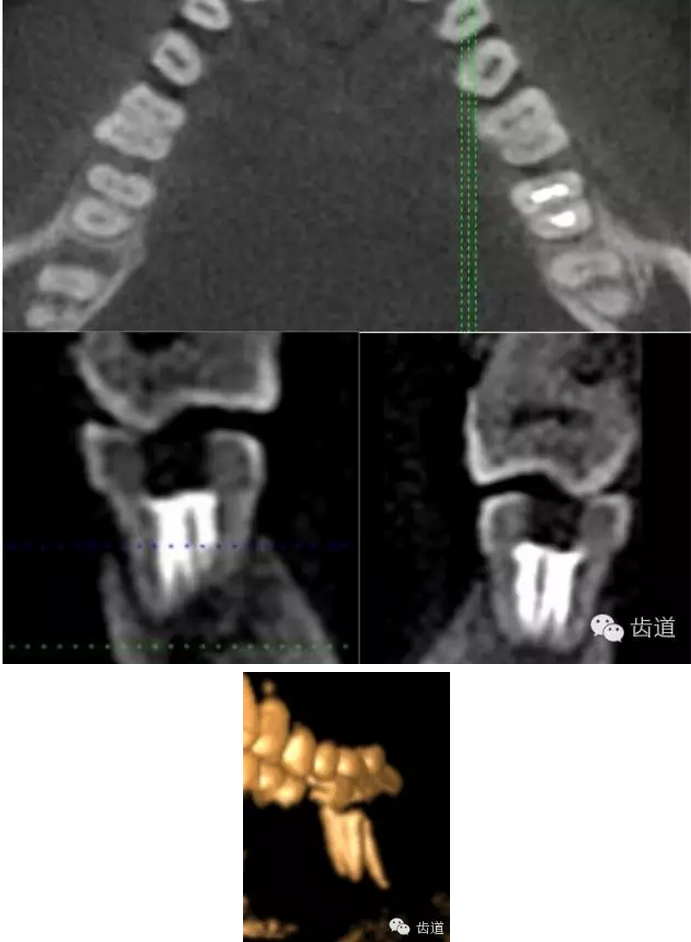

上頜第一磨牙:多為3-4個根管,MB2發(fā)生率約為60%;

上頜第二磨牙:與上頜第一磨牙相似,多為3根管,偶見雙鄂根管;